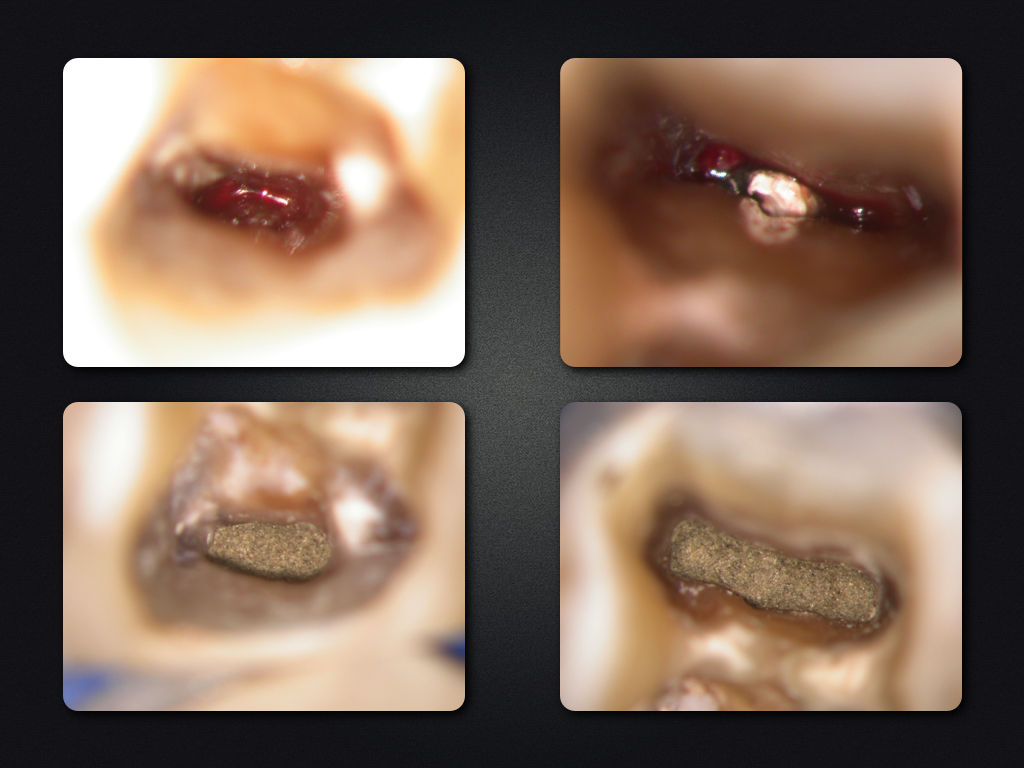

36D.004

WSR ohne WF